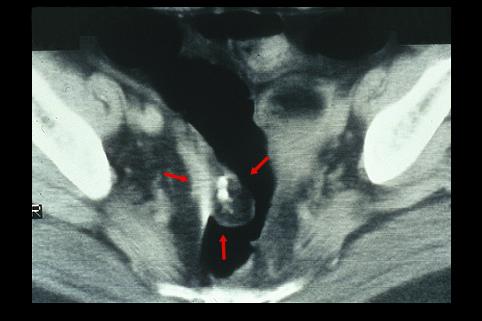

난소의 기형종이 직장의 점막면을 압박하여、천파한 대장의 종양양 병변

종양양 병변/근접장기로부터의 침윤

대장/직장

CT

30~34